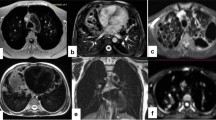

All patients with CPFE were subjectively correctly identified on LGE-MRI. Figures 2 and 3 provide imaging examples in two patients with CPFE of LGE in regions of pulmonary fibrosis in the lower lobes and an absence of LGE in regions of emphysema in the upper lobes. The contrast-to-noise ratio was 30.1. Table 2 shows the median SI in regions of fibrosis and emphysema. Qualitatively, emphysema showed no evidence of LGE-MRI enhancement in any patient. Quantitatively, significant differences were found in median SI in regions of fibrosis compared to regions of emphysema (25.8, IQR 18.4–31.0 versus 5.3, IQR 5.0–8.1, p < 0.001). ROC analysis of SI in fibrotic areas in the lower lobes compared to emphysematous areas in the upper lobes in CPFE patients showed an area under the curve of 0.95, p < 0.0001. Using a SI value of ≥ 12 resulted in a sensitivity of 95% and specificity of 100% in differentiating fibrosis from emphysema in CPFE patients (Fig. 4). The percentage of SI increase in pulmonary fibrosis compared to emphysema was 278.5% while the percentage of density increase in pulmonary fibrosis compared to emphysema on HRCT was 36.4%. Significant differences were seen between LGE-MRI and HRCT in the extent of reticulation (12.5, IQR 5.0–20.0 versus 15.0–26.3, IQR 5–40, p = 0.038) and honeycombing (5.0, IQR 0.0–10.0 versus 20.0, IQR 10.6–20.0, p = 0.001) but not in traction bronchiectasis (10.0, IQR 5–15 versus 15.0, IQR 5.0–15, p = 0.878 (Table 3).

Fifty-seven-year-old man with progressive breathlessness, FEV1 2.4 L/s, LAV 7.6%. a Axial high-resolution computed tomography showed moderate centrilobular emphysema in the upper lobes (arrows). b It was unclear at multidisciplinary conference whether the abnormal regions in the lower lobes (arrows) represented emphysema or fibrosis. c Late gadolinium-enhanced magnetic resonance imaging of the upper lobes showed no contrast enhancement, but in d, definite contrast enhancement in the abnormal regions in the lower lobes (arrows) was consistent with fibrosis. FEV1, Forced expiratory volume in one second; LAV%, Low attenuation value percent